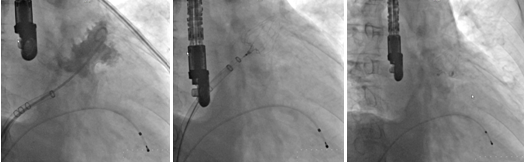

左心耳造影图像 左心耳封堵器释放前 左心耳封堵器成功释放后

术前左心耳CT重建左心耳形态